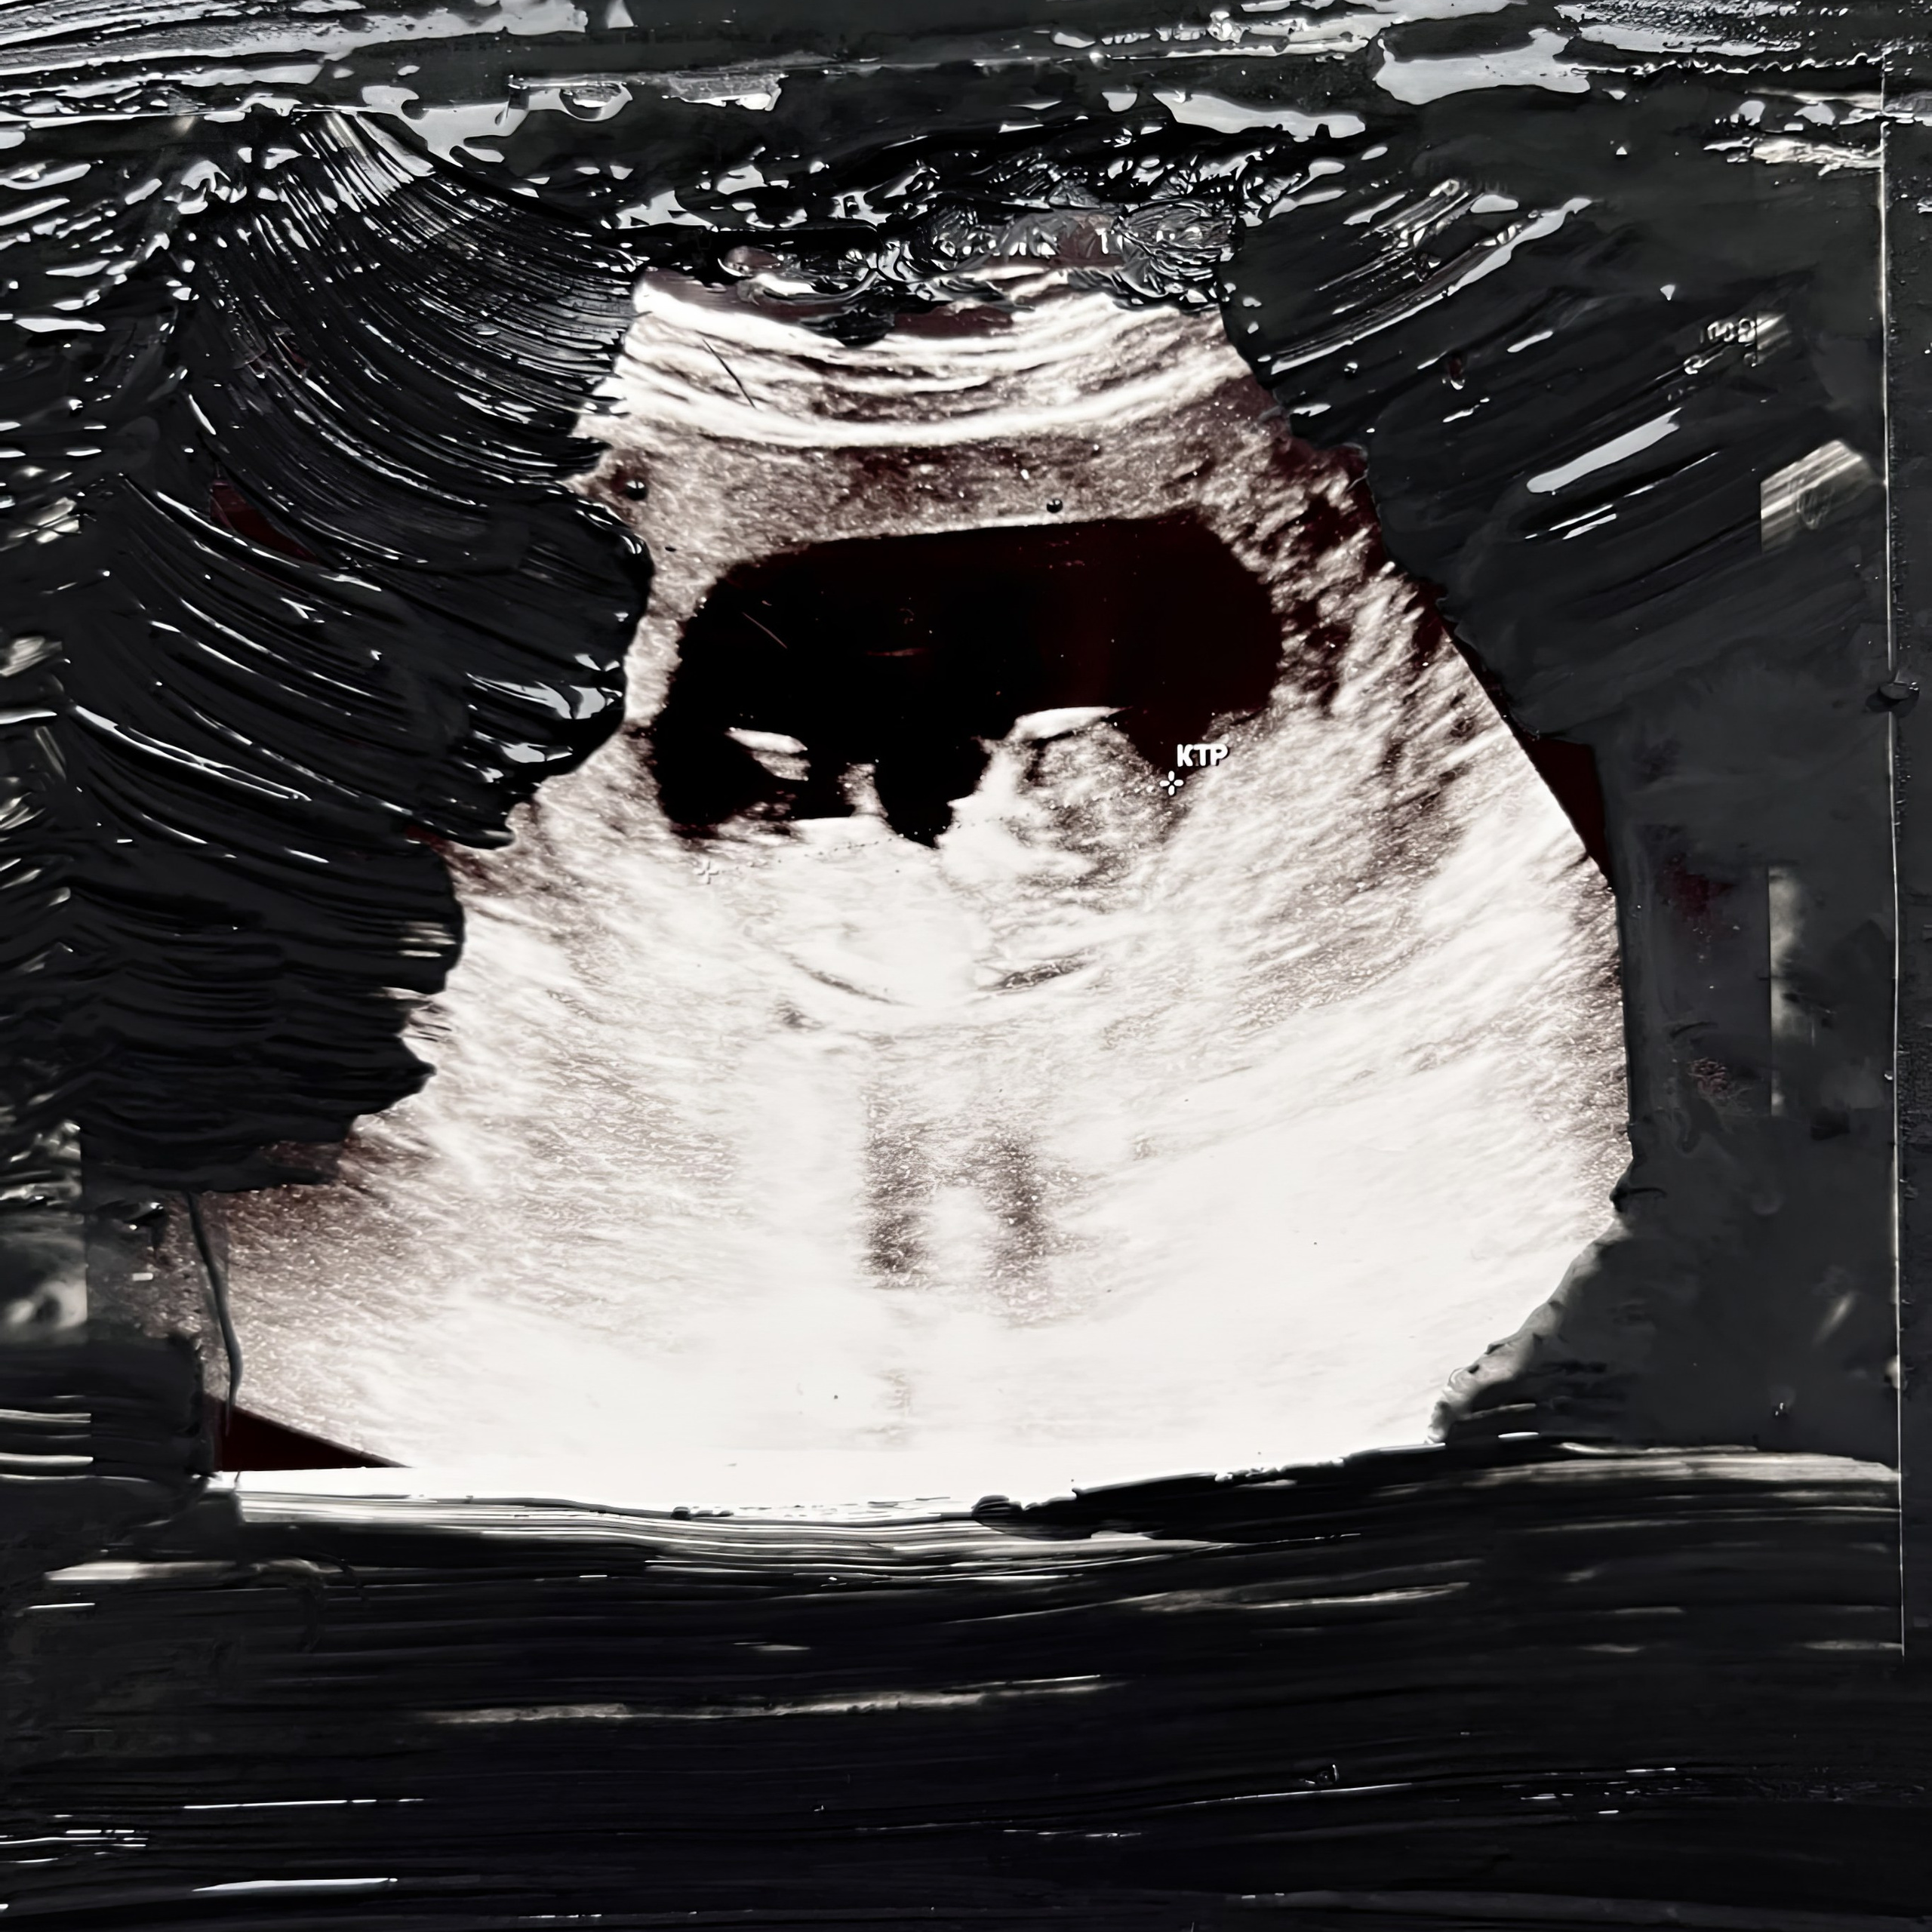

Я заболела ковидом на 40-й неделе беременности. Мой сын родился в инфекционной больнице — и его сразу забрали у меня. Впервые мы встретились только через месяц.

Так я в 27 лет, а он в 1 день жизни узнали, что человек рождается один.

Эта история об этом ощущении.